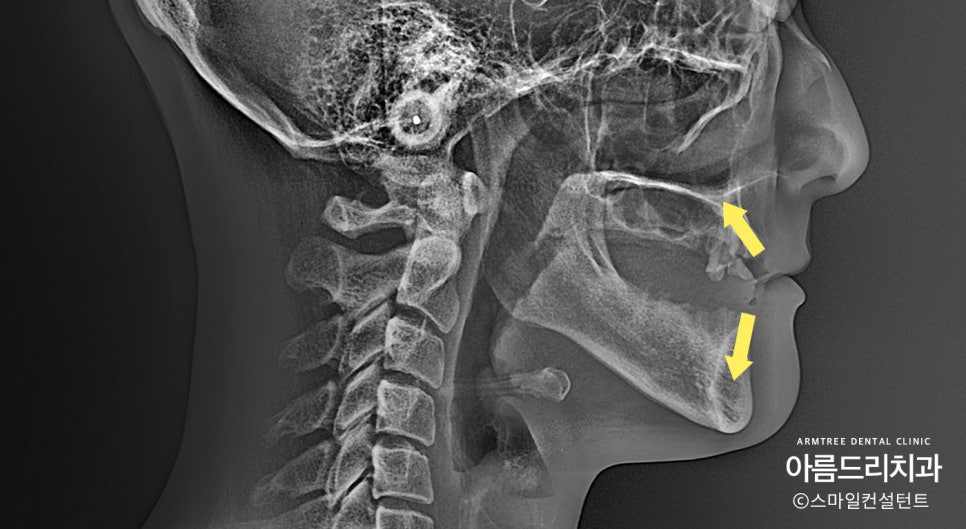

옆 얼굴 엑스레이를 보시면 윗입술 각도가

많이 말려들어간 것(노란화살표)이 보입니다.

윗턱뼈는 녹아서 없어질 때 화살표 방향으로 흡수가

일어나며 그로 인해 윗입술이 말려들어가고 입술이

얇아지며 코 아래쪽이 푹 꺼진 듯한 얼굴로 변합니다.